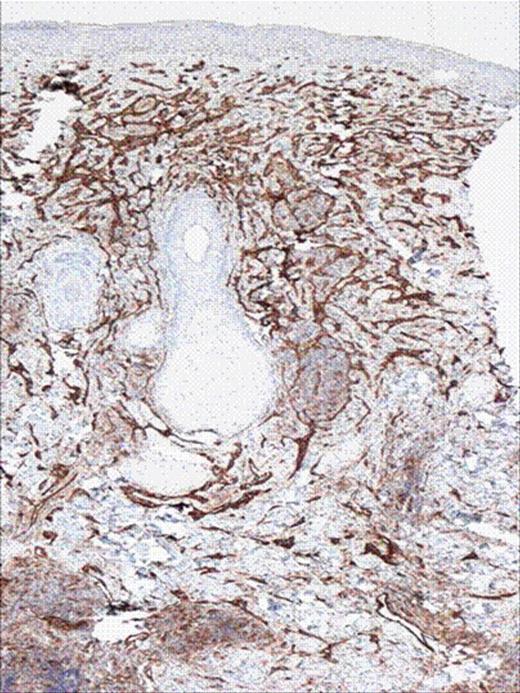

CD 31 stains of the skin biopsy showing vascular tumor.